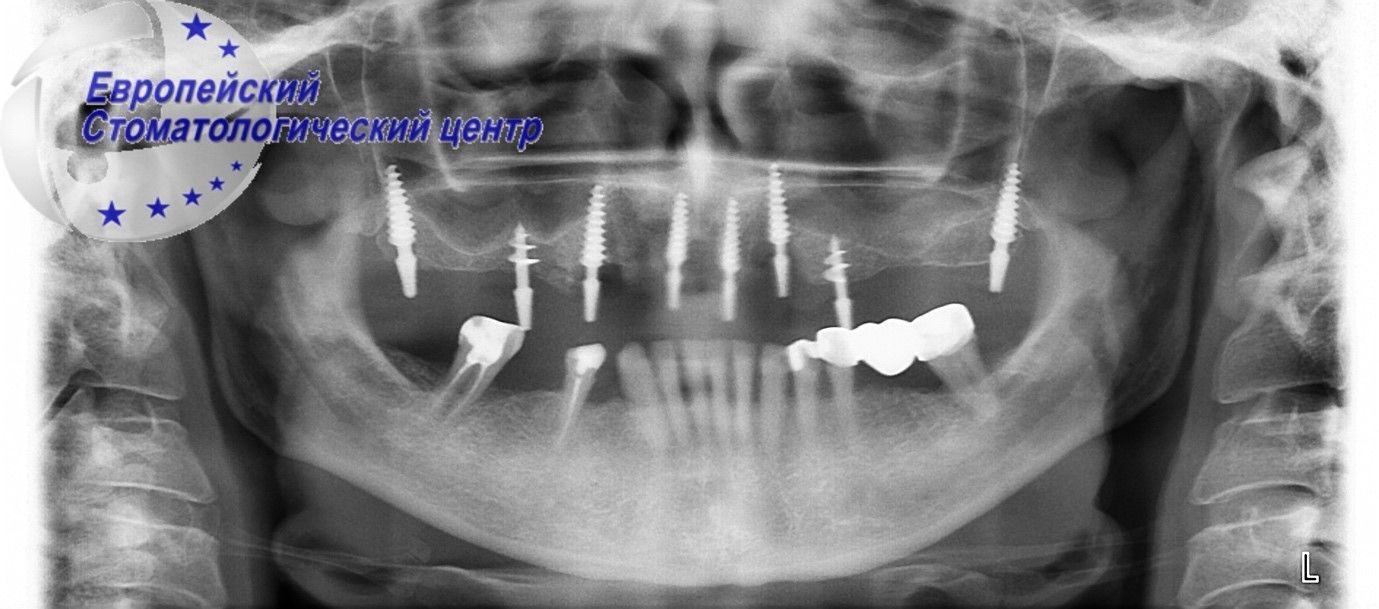

В Европейский стоматологический центр обратился пациент с жалобами на сильную подвижность зубов на верхней челюсти и нижней челюсти, неприятный привкус и запах в полости рта, невозможность прожёвывать пищу и связанный с этим эстетический дефект (см.Рис 1-2).

Рисунок 2

Установлен диагноз, прогрессирующий генерализованный парадонтит. Было принято решение об удалении всех имеющихся зубов с немедленной имплантацией. Операцию по установке имплантов осложняло еще и присутствие инфицированных тканей в полости рта. После удаления зубов была произведена дезинфекция лазером и кюретаж лунок удаленных зубов. Врачам Европейского стоматологического центра, удалось в одно хирургическое вмешательство удалить поврежденные зубы на верхней и нижней челюсти, малоинвазивно, без дополнительных разрезов и осложнений установить 17 имплантов, и через день установить временные несъемные ортопедические конструкции (см.Рис. 3-4).

Рисунок 3

Рисунок 4

В настоящее время пациент ожидает полной интеграции имплантов и установки постоянных несъемных конструкции. Быстрая (за 3 дня) реабилитация пациента достигнута благодаря многолетнему опыту, постоянному совершенствованию, и наличию современного стоматологического оборудования в Европейском стоматологическом центре.